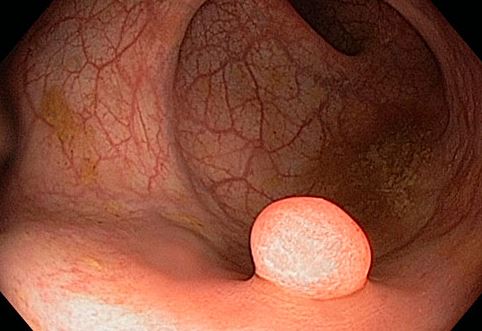

Βιταμίνη D και καρκίνος του παχέος εντέρου

Είναι πολύ νωρίς για να γίνουν οριστικές διαπιστώσεις για το ρόλο της βιταμίνης ως βιταμίνη που μάχεται τον καρκίνο γενικά. Ωστόσο, νεότερες μελέτες δείχνουν ότι τα άτομα με υψηλότερα επίπεδα βιταμίνης D στο αίμα τους μπορεί να έχουν μικρότερο κίνδυνο για καρκίνο του παχέος εντέρου.